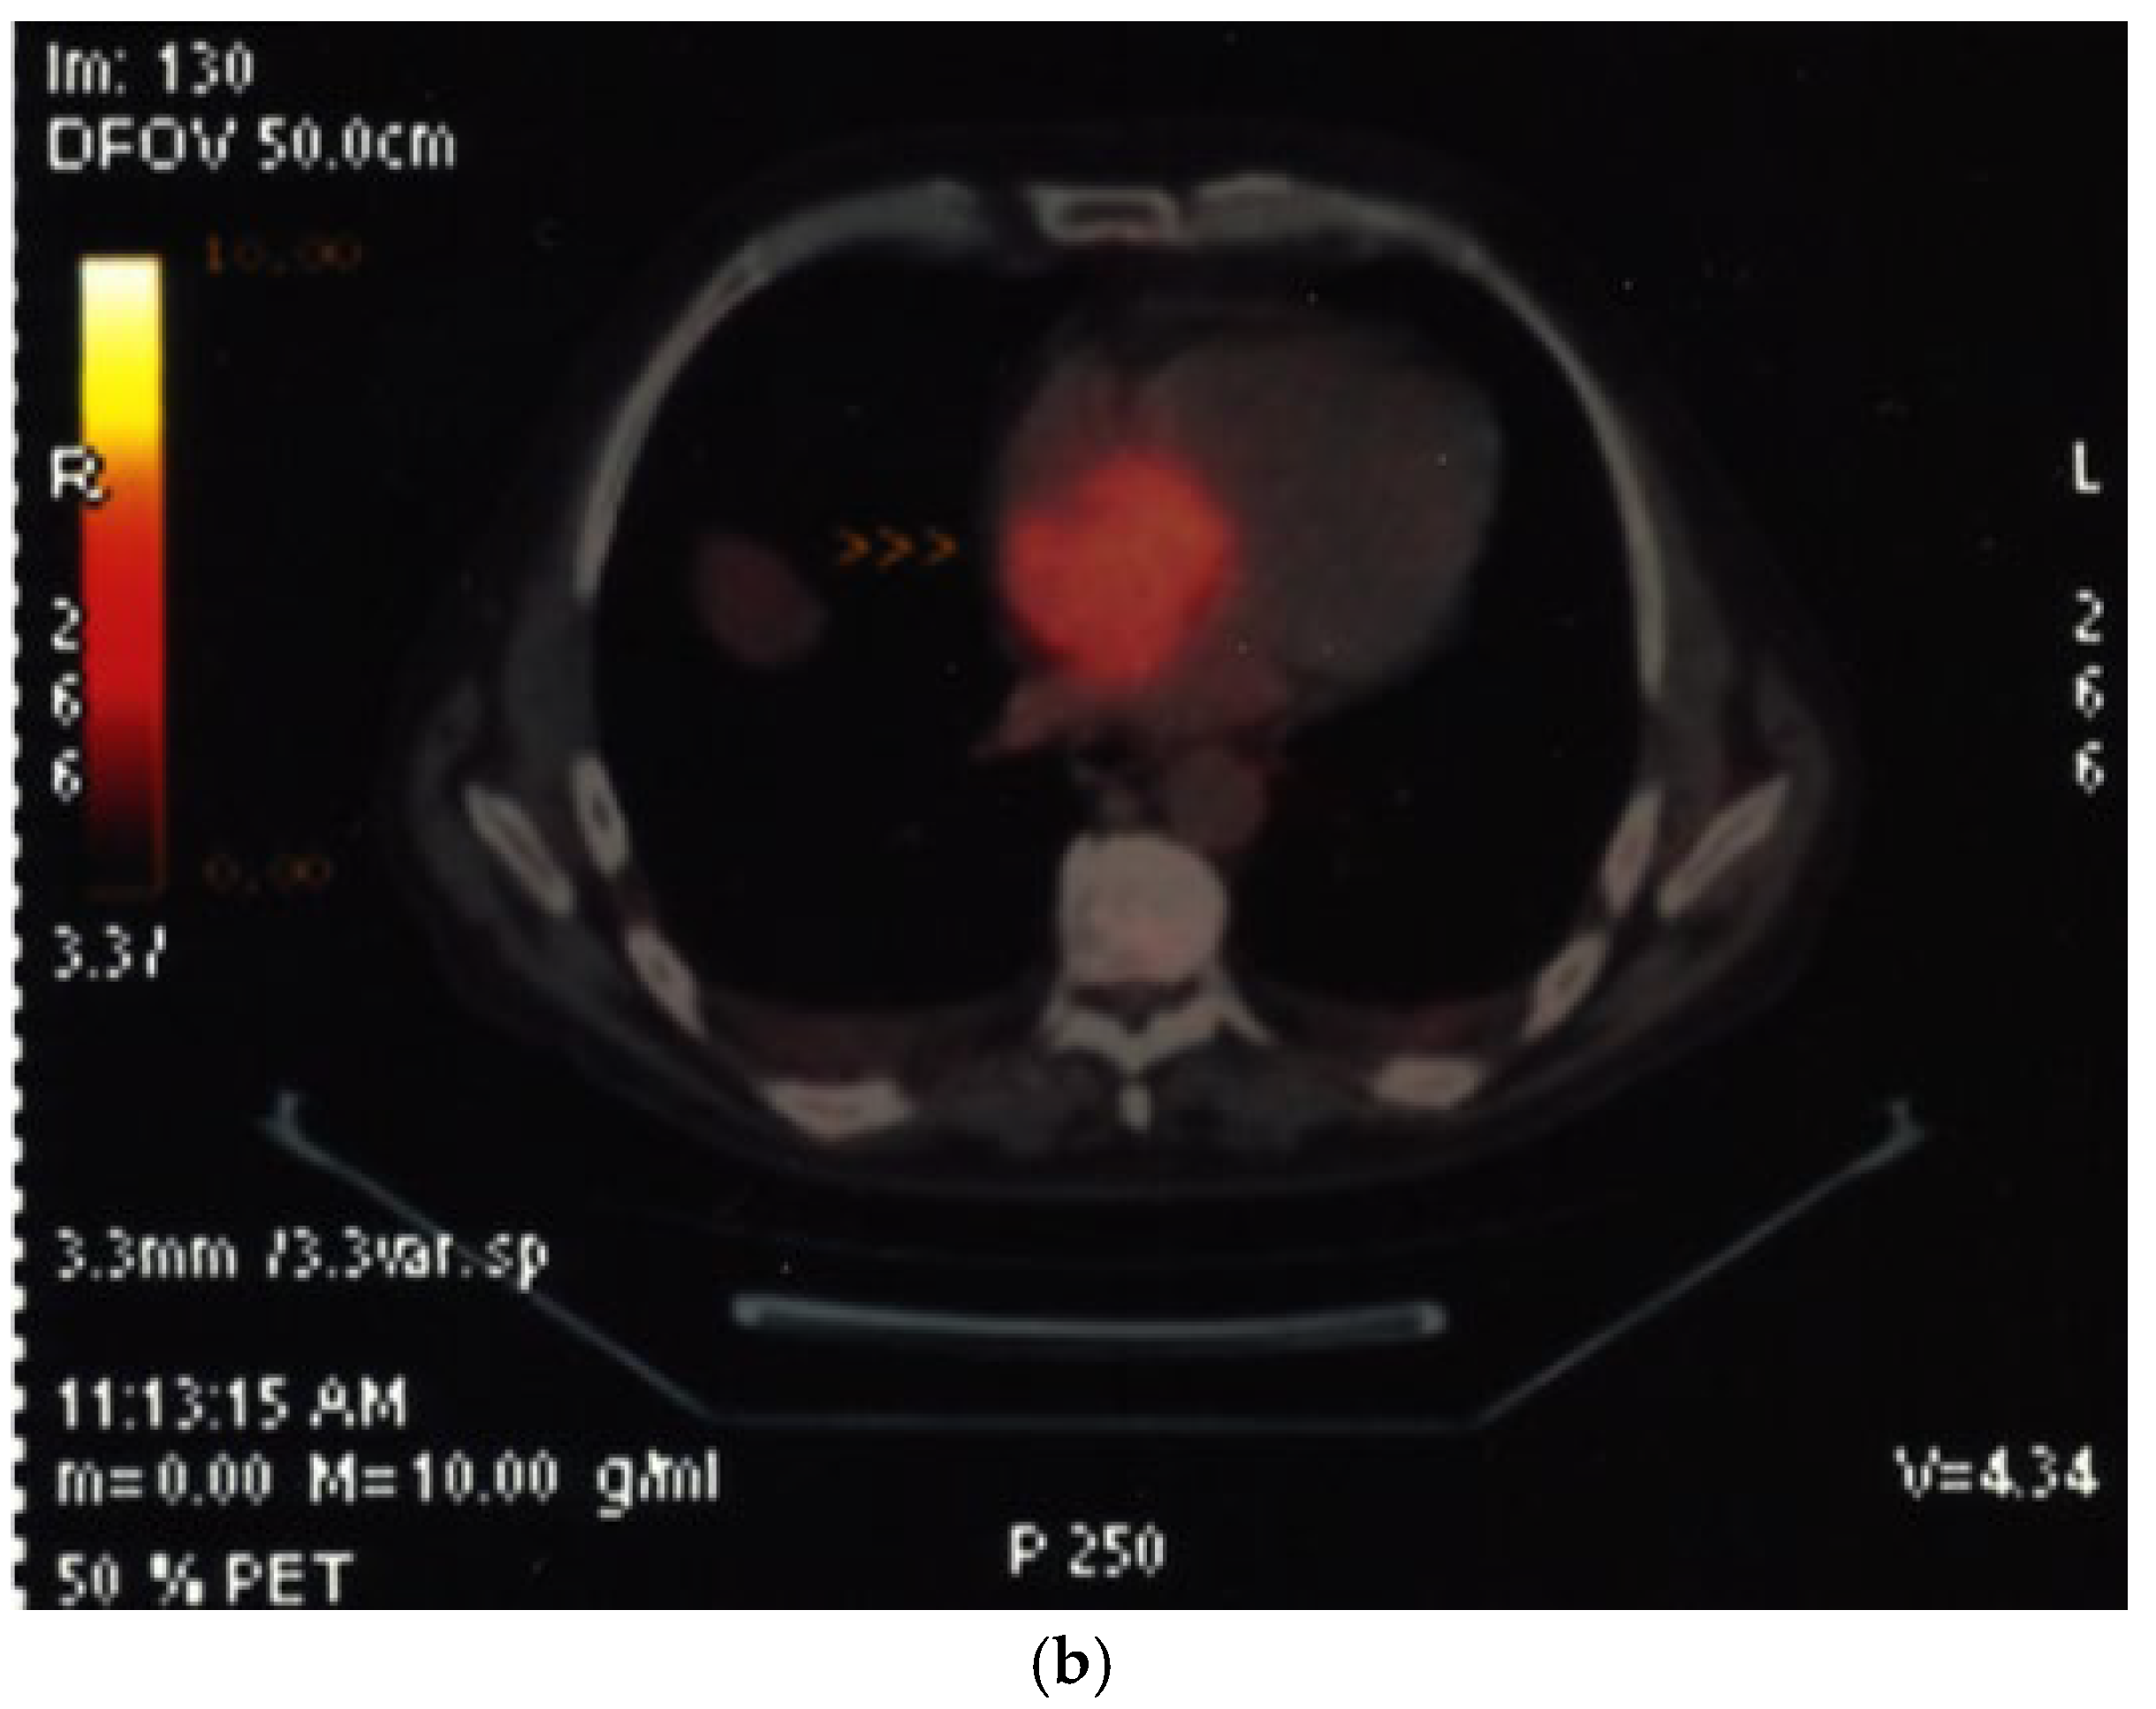

7. Myocardial Perfusion—Fundamentals and Practical Application

7.1. Background and Indications

| Viability in chronic CAD |

| No reflow in acute MI |

| Cardiac tumors |

| Assessment of myocardial ischemia/viability during stress echocardiography |

| Imaging method | Low-MI-contrast-specific imaging—Flash–Replenishment |

| Imaging planes | standard apical views additional modified views to optimize perfusion imaging in basal anterior/lateral segments or views to optimize the display of suspected tumors |

| Contrast application | Infusion bolus injection acceptable for demonstration of vascularization of a cardiac tumor |

| Typical findings | Normal myocardial perfusion: homogeneous opacification of the segment, contrast replenishment within 5 s after flash (2 s during stress) Abnormal perfusion: delayed contrast replenishment, perfusion defect, often combined with abnormal wall motion Tumors may show patchy opacification and include dark areas due to necrosis |

| Alternative imaging | Doppler velocity measurements (see above), nuclear imaging (SPECT, PET), cardiac MRI for assessment of myocardial perfusion and viability Tumors: MRI provides tissue characterization and should be performed unless there is typical myxoma (attached to the interatrial septum) |